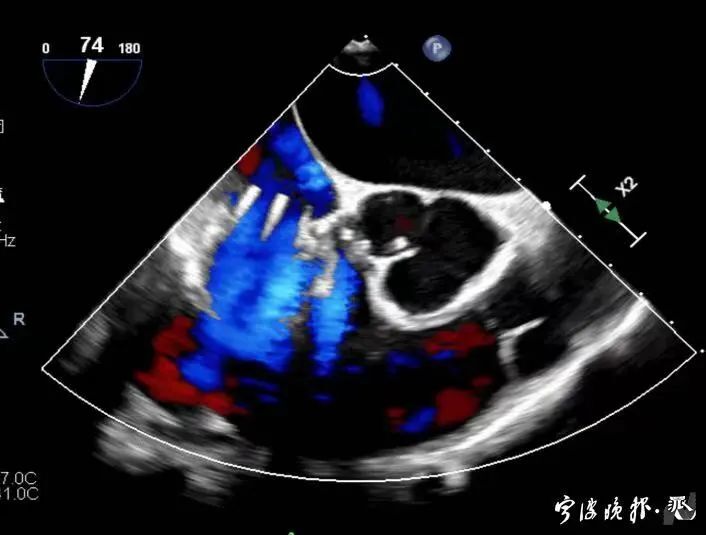

術前食道心超示三尖瓣重度反流